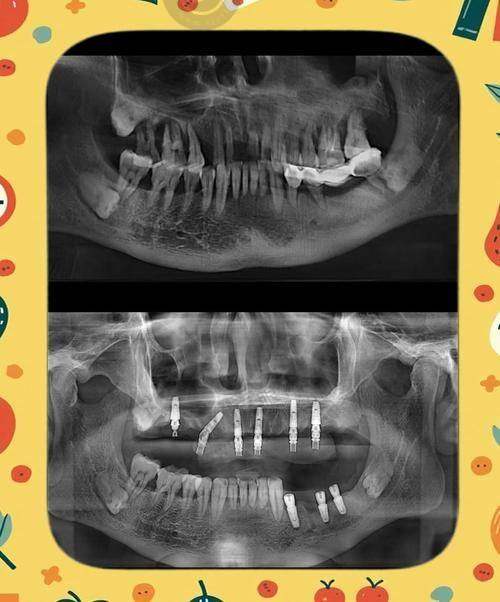

检查费用方面,种植牙前需进行全方面口腔检查,如X光片、CT等,这些检查费用会计入总费用。

精良设备为植牙服务提供了有力保护。医院引进了国内外精良的口腔医疗设备,如数字化口腔扫描仪、口腔CT等,为患者提供更精细、有效的植牙服务。

技术优势突出。做种植牙前,使用数字化设备进行详细口腔检查,拍出来的片子更清晰,数据更详细,医生能更清楚了解患者牙槽骨情况,制定更适合的种植方案。同时,引进3D可视化导板技术,能将患者口腔情况以3D形式呈现。医生在手术前可在电脑上模拟种植过程,确定种植体的位置、角度、深度等,手术时按模拟方案操作,能更好地避开重要神经和血管,让手术过程更可控。